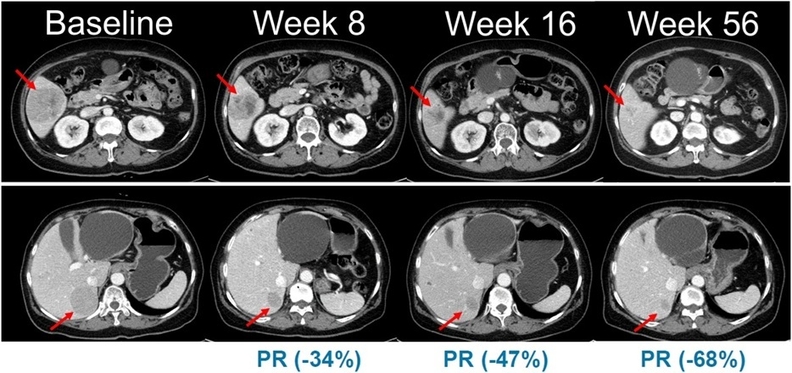

임상 2상은 총 45명의 환자를 대상으로 벨바라페닙과 MEK 억제제 ‘코비메티닙’ 병용요법의 유효성과 안전성을 평가하는 다기관·단일군 시험으로 진행된다. 흑색종은 치료 옵션이 제한적이고 재발 위험이 높은 난치성 암이다. 특히 NRAS 돌연변이 흑색종은 국내외에서 허가된 표준 치료제가 없어 의료적 미충족 수요가 매우 높은 영역이다. 현재 일부 환자에게는 치료목적사용 승인을 통해 제한적으로 투약되고 있다.

벨바라페닙은 한미약품이 자체 개발한 경구용 표적 항암제로, 종양 세포 성장과 증식에 관여하는 MAPK 경로 중 RAF 및 RAS 유전자 돌연변이를 선택적으로 억제하는 기전을 갖고 있다. 기존 BRAF 저해제가 단일체 억제에 그친 것과 달리, 벨바라페닙은 BRAF 및 CRAF 이합체까지 함께 저해하도록 설계돼 내성 문제 극복 가능성을 높였다. 이에 따라 코비메티닙과의 병용요법은 보다 폭넓은 유전자 변이 환자군에서 치료 효과를 기대할 수 있는 전략으로 주목받고 있다.